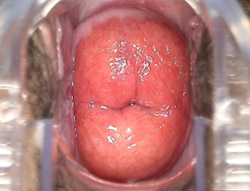

三度重度宫颈糜烂图片

根据病变程度的不同,宫颈糜烂的外表特征也有很大差异。临床工作中常将宫颈表面柱状上皮生长缓慢,仅为较正常的单层柱状上皮覆盖,外观平坦,表面潮红、光滑的这一类型称为单纯型糜烂。如柱状上皮生长速度快,并向间质生长,形成腺体增生、扩张,肉眼观表面呈细小颗粒状,称为颗粒状糜烂,或滤泡型糜烂。如间质增生明显,宫颈表面形成许多小的突起或沟回,肉眼观表面高低不平,此种宫颈糜烂图片所示称为乳头状糜烂